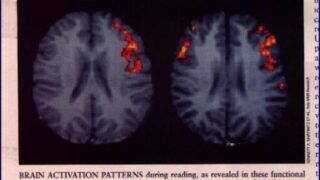

言葉を理解する際に

男性は左脳のみを使っているのに対し、

多くの女性が左右の脳を使っていることが

MRI(磁気共鳴映像装置)を使った実験で確認されています。

言語野

女 右脳左脳

男 左脳のみ